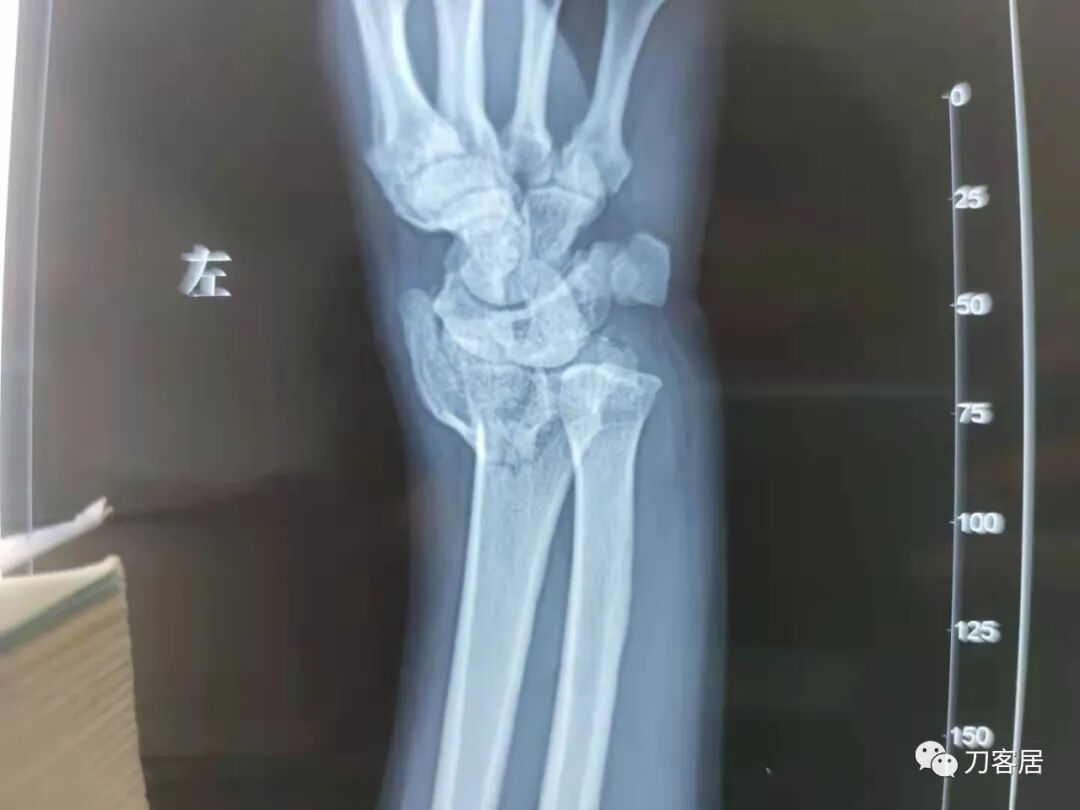

1.  这是一个很简单的6岁儿童无移位的尺桡骨远端骨折。没有皮肤损伤,没有移位,没有骨折碎块儿。

2.  这个骨折处理起来也很简单,单纯的打石膏托或者中医的小夹板,或者正规的包括腕关节和肘关节的管型石膏外固定4周即可治愈该骨折。实在不行,如果这个孩子比较听话,不太调皮的话,用一本书,一个三角巾悬吊固定4周,都可以治愈该骨折。但是给这个患者用外固定架做了手术,而且桡骨远端的几颗克氏针距离骨折线太近,其中一枚克氏针进入到骨折间隙内。从这个术中图片来看,术者的外固定手术技术也有待于进一步的提高。毕竟术者应该还很年轻。从X线片来看,前臂及手的尺侧有不透光影,应该还使用了外固定石膏绷带托,而且我猜测应该是高分子的石膏绷带托,这个是纯属猜测,不一定是对的,不过如何解释前臂尺侧的不透光影呢?如果真是用了石膏绷带外固定的话,那为啥要做手术呢?外固定架术后就不该再用石膏绷带托辅助了。

这个病例,6岁的孩子,尺桡骨骨折在同一个平面,且都为小斜行骨折,不是螺旋形,不是粉碎性,不是成角移位性,属于稳定性尺桡骨双骨折,根本就没有任何手术的适应症。